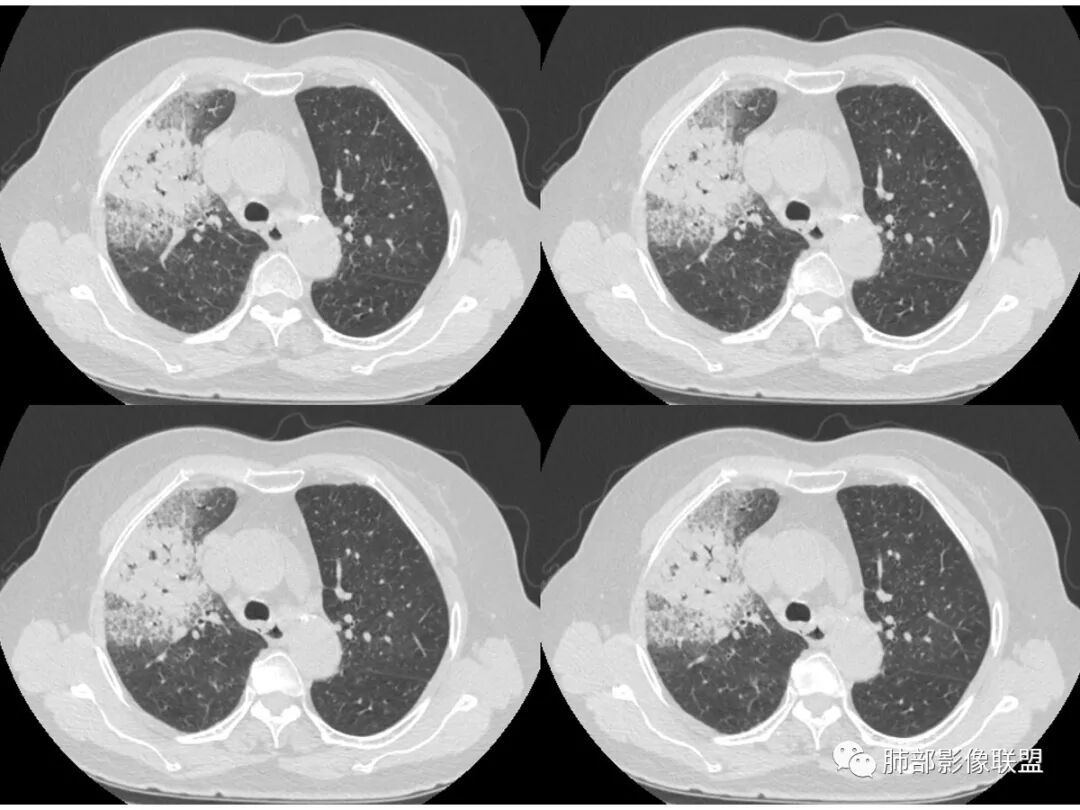

右肺上叶大片状阴影,内见僵硬的支气管,部分支气管轻度扩张,内见一空洞和液平,病灶边缘可见磨玻璃影,首先考虑恶性病变,粘液性腺癌伴感染可能。

老年女性,右肺上叶大片实变及磨玻璃密度影,磨玻璃边缘清晰,内可见小叶间隔增厚,内可见空洞,似可见分隔,叶间裂局部膨隆,纵膈窗,没有增强,枯树枝不明显,肺炎型肺癌可能,鉴别大叶性肺炎,结核?

胸CT:右肺上叶实变内可见支气管充气征,近端支气管狭窄,远端扩张,周围可见毛玻璃影,右肺中叶支气管闭塞,并可见气道壁钙化,右肺中叶体积缩小,实变内可见空洞,并可见气液平面,空洞周围可见毛玻璃样影,右肺下叶支气管开口狭窄,右肺门淋巴结肿大。纵隔窗可见病灶与壁层胸膜间隙增宽,考虑良性病变-----感染性病变------TB?

老年女性,右肺中上叶病灶,血象不高,血沉高,TB dna阴性,上叶尖端病灶,紧贴胸膜,边界似清非清,中间可见实变,内见枯树枝征,首先考虑粘液腺癌可能性大。患者右肺中叶见空洞、气液平,病灶没多发空洞,可见气液平,考虑合并TB感染。

老年女性,无诱因咳嗽咳痰,白色粘液痰,抗炎治疗无好转,右肺多叶磨玻璃影,其内见枯树枝征,磨玻璃边界清,中间见实变影,且部分实变影内见空洞或局部支气管扩张,内壁光整,无纵隔淋巴结肿大,常规考虑粘液性腺癌,感染性病变待排,细菌性的排除,白细胞不高,不太支持,建议支气管镜检。

1.右上肺大片状影,周围有磨玻璃影,支气管截断征、枯枝征、远端支气管充气征,可见多个大小不等囊泡(支气管阻塞活瓣作用形成),病灶有少许收缩力感,叶间裂被稍牵拉内移;

病史老年女,白痰;影像实变,ggo多数边界清,病灶下缘部分不清,枯树枝,支气管近端阻塞、僵硬,病灶跨叶;病灶内空洞,有液平;间质增厚有结节感;肺炎型肺癌大于干酪性肺炎。

老年女性,慢性病程,咳嗽伴白色粘液痰,无发热腹痛,糖尿病,白细胞及C反应蛋白不高,血沉快,铁蛋白高。胸部CT,右肺上叶大片状实变伴磨玻璃密度影,边界不清,边缘局部膨隆,叶裂弧形下坠,实变影宽基底与胸膜相贴;右肺下叶前基底段见类似病灶;右肺中叶不张并空洞形成,空洞内见气液平面;综合考虑右肺上叶及下叶肺炎型肺癌,右肺中叶结核。

白色粘液痰,枯树枝,支气管僵直,有空洞,磨玻璃,叶间裂膨隆、下坠,吴婧老师的肺炎型粘液性腺癌十大特点中占了好多条,所以考虑粘液腺癌,就差增强看看强化如何,血管如何了

患者老年女性,亚急性起病,胸部CT:右肺上叶大片实变,可内见坏死性空洞,可见mGGO,GGO边缘清晰,局部彭隆,内见支气管充气征,可惜没增强,粘液腺癌要考虑,但病灶明显是内朝外不支持,综合考虑结核,建议查痰找抗酸杆菌、气管镜

老年女性,咳白色粘液痰,右肺跨叶大片高密度影,密度不均匀,其内见支气管枯树征,有空洞,边缘部分清楚,叶间裂有下坠膨隆感。考虑粘液腺癌,鉴别干酪性肺炎